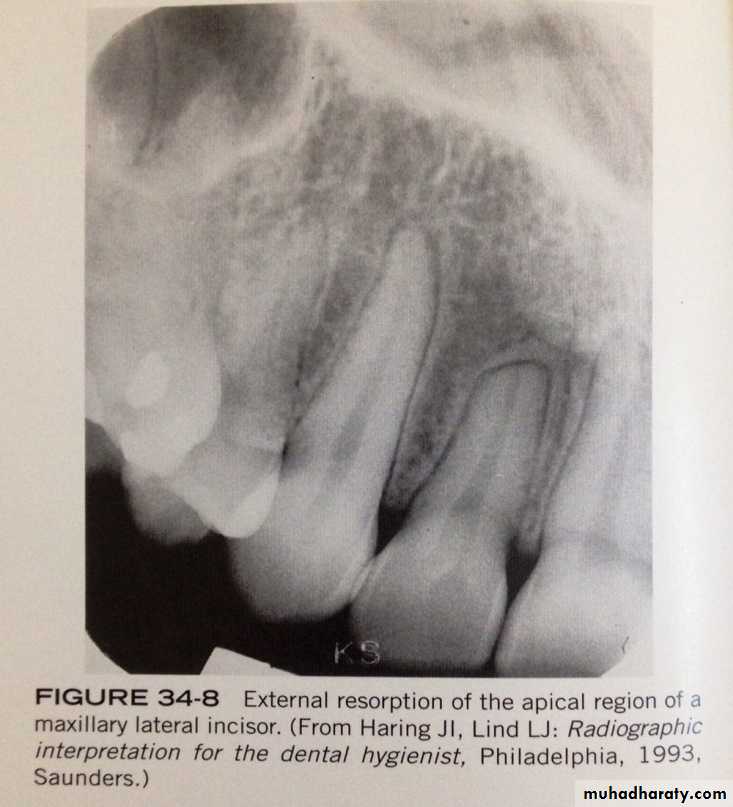

External Resorption

is seen a long periphery of the root surface and is often associated with abnormal mechanical force, trauma, chronic inflammation, reimplanted teeth, tumors, cysts and impacted teeth.

- external resorption most often affect the apices of teeth, the apical region appear blunted, and the length of the tooth appear shorter than normal.- its asymptomatic and there is no effective treatment to external resorption.